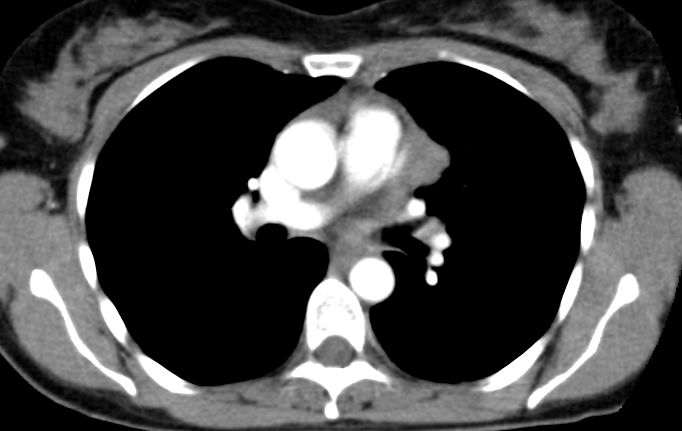

48-jährige Frau mit Subclavia - Thrombose links. Ursache war ein großzelliges B-Zell-Lymphom des oberen Mediastinums.![]() |

Kompression der V. subclavia links.![]() | |